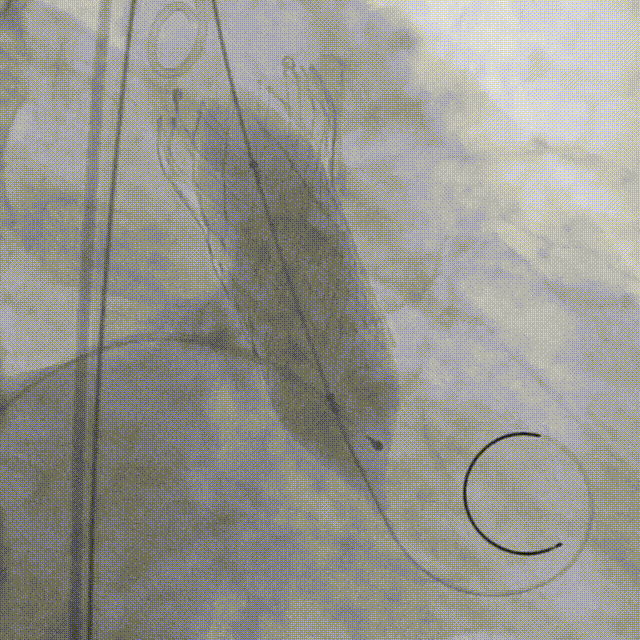

瓣膜释放到2/3的位置(手柄上有触觉提示)

瓣膜释放到80%并造影评估深度合适(少量反流,瓣膜形态椭圆)

左冠切线位造影评估冠脉风险(左冠血流灌注良好)